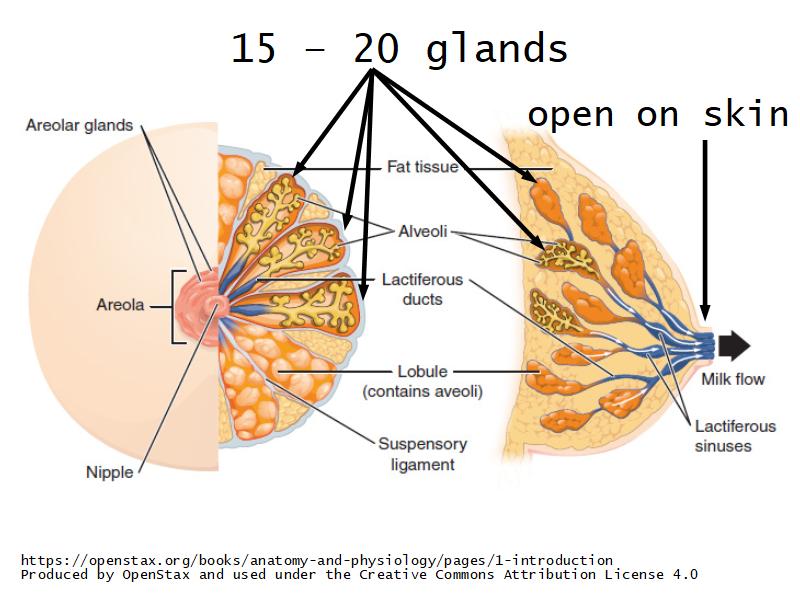

Mammary gland

Write short notes describing the structure of the mammary gland.

(5)

Mammary gland

- Compound tubuloalveolar gland

- 12 - 20 glands

- Each with own lactiferous duct

- Each with own lactiferous sinus

- Opens on skin at apex of nipple